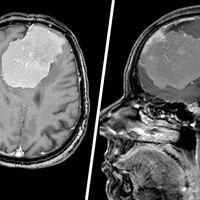

Пациентка поступила в медучреждение с подозрением на инсульт: у нее наблюдалась сильная слабость в правой руке, а также проблемы с речью. На томографии врачи исключили инсульт, но обнаружили в мозге женщины новообразование размером с грейпфрут.

«Дополнительное исследование с контрастом показало, что опухоль окутывала магистральные сосуды Велизиевого круга – переднюю мозговую артерию, а также прорастала в переднюю треть сагиттального синуса и закрывала его», — рассказали в пресс-службе.